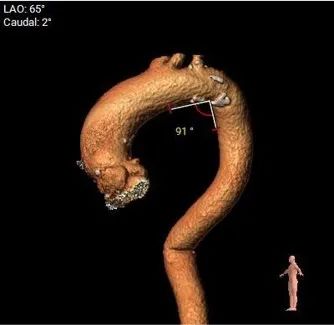

主动脉弓评估

• 非横位心,升主无明显扩张,弓部宽度角度可,应用TaurusElite 输送器可顺利过弓、跨瓣;弓顶部存在钙化,小心通过防止钙化脱落